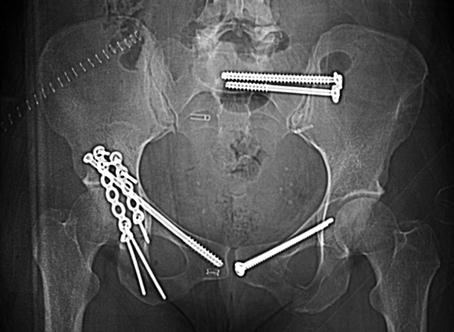

This patient (previously seen in Fig. 3) had a right transverse acetabular fracture-dislocation as well as left pubic ramus fracture and SI joint disruption. The acetabular fracture was treated operatively using a posterior Kocher-Langenbeck exposure. The reduction was accomplished after cleaning the fracture surfaces and then clamping the transverse fracture. A cancellous lag screw was inserted percutaneously in the superior pubic ramus, and then two malleable plates were applied posteriorly to stabilize the transverse fracture. The SI joint injury and pubic ramus fracture were treated with closed reduction and then screw fixation. An initial iliosacral cancellous lag screw compressed the SI joint, and the subsequent fully threaded cancellous screw provided additional support. The acetabular lag screw, iliosacral screws, and the retrograde superior pubic ramus screw were all inserted percutaneously using biplanar fluoroscopic imaging